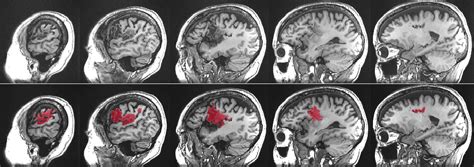

Let’s talk about causes of aphasia . Understanding what triggers this language disorder is super important for prevention and treatment strategies. The primary cause of aphasia is damage to the language-dominant areas of the brain. For most people, the left hemisphere of the brain is responsible for language functions. When these areas are injured, aphasia can result. The most common culprit, as we’ve touched upon, is a stroke . Strokes occur when blood supply to a part of the brain is interrupted, either by a blockage (ischemic stroke) or by bleeding (hemorrhagic stroke). This lack of blood flow deprives brain cells of oxygen, causing them to die. Depending on which part of the brain is affected, language abilities can be severely impacted. Another significant cause is Traumatic Brain Injury (TBI) . TBIs can happen from blows to the head, falls, or accidents. The widespread nature of the damage in a TBI can affect various brain functions, including language. Brain tumors can also lead to aphasia . Whether the tumor is malignant or benign, its growth can press on or invade brain tissue, disrupting normal function, including language processing. Brain infections , such as encephalitis (inflammation of the brain), can also cause damage to language areas. Lastly, neurodegenerative diseases are a cause, particularly Primary Progressive Aphasia (PPA). PPA is a group of brain disorders caused by specific types of dementia that target the brain’s language networks. Unlike other causes where aphasia might appear suddenly, PPA is typically a gradual decline. Each of these causes of aphasia presents unique challenges in terms of diagnosis, treatment, and prognosis. Knowing the cause helps medical professionals tailor the approach to managing aphasia , aiming to restore as much language function as possible and improve the quality of life for those affected. It’s a complex puzzle, and identifying the root cause is a critical piece.

Now, let’s get into the nitty-gritty: the types of aphasia . Because aphasia is caused by damage to different parts of the brain, it doesn’t just show up as one single problem. Instead, it’s classified into various types, each with its own set of characteristics. This classification helps speech-language pathologists (SLPs) understand the specific challenges a person is facing and develop targeted therapy. The two main categories are often fluent aphasia and non-fluent aphasia , with further subtypes within each.

Fluent Aphasia

In fluent aphasia , individuals can speak easily and smoothly, often at a normal rate. However, what they say may not make sense. They might use made-up words (neologisms) or substitute incorrect words (paraphasias). Comprehension is often impaired. The most well-known type of fluent aphasia is Wernicke’s aphasia . People with Wernicke’s aphasia can speak fluently but often produce nonsensical speech, sometimes referred to as a